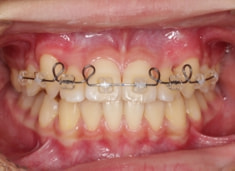

治療前

治療開始時